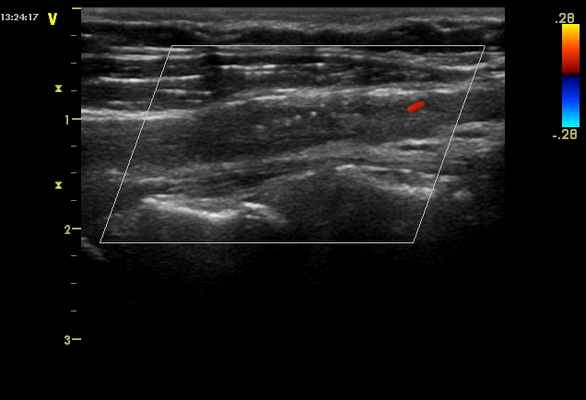

При проведении дуплексного сканирования БЦА - эхографические признаки хемодектомы (параганглиома, нехроматоффинная параганглиома, каротидная хемодектома) - доброкачественное новообразование сонного гломуса.

А рис. 1 – ОСА справа. На рисунках 2, 3 - видно как опухоль охватывает внутреннюю сонную артерию справа, плотно спаяна с адвентицией. Пациентка в экстренном порядке направлена на консультацию к сосудистому хирургу в ВМА им. С.М.Кирова.